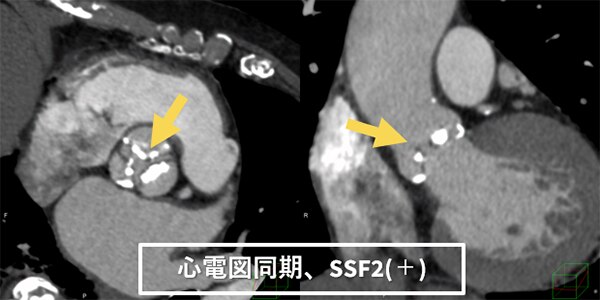

過去の検査時はどうしても至適心位相を探すため、segment再構成等を繰り返し撮影と画像検索を両立するのは困難でした。しかし、最適心位相検索に「Smart Phase」、モーションアーチファクトを抑制する 「SnapShot Freeze2.0(以下SSF2)」を併用することにより、最適心位相の検索をほぼ自動で行えるようになりました。結果、心臓CTの最適心位相検索に時間を割く必要がなくなり、人員配置の最適化を行えるようになると考えています。